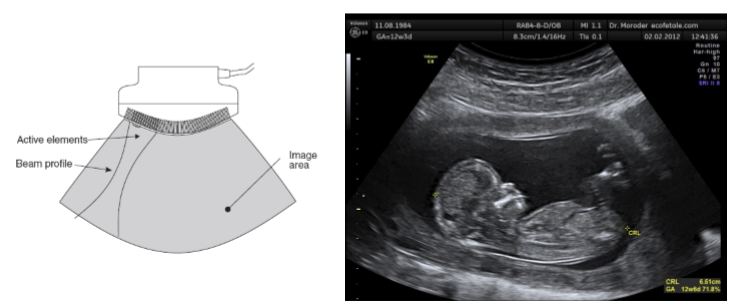

curvilinear array

elements are arranges in a curve

fired in groups + electronically focused

used in abdominal and obstetrics